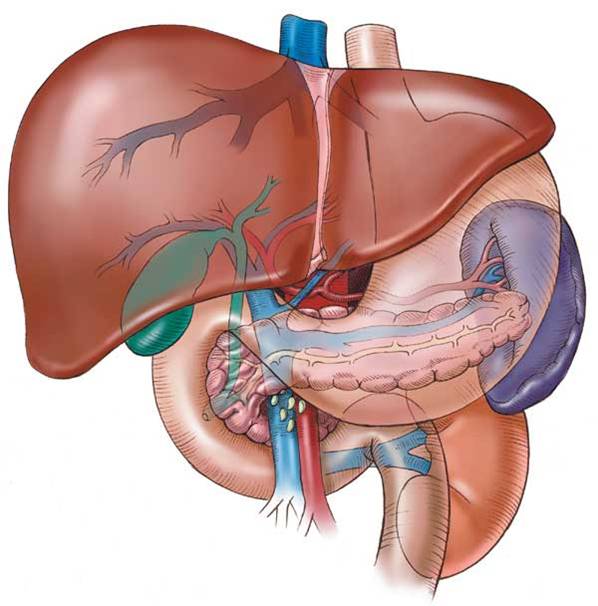

İbrahim Saraçoğlu karaciğer yağlanması

karaciğer yağlanması, karaciğer yağlanması bitkisel tedavi, karaciğer yağlanması ibrahim saraçoğlu, bitkisel karaciğer yağlanması tedavisi, ibrahim saraçoğlu karaciğer yağlanması, ibrahim saraçoğlu karaciğer yağlanması kürü, ibrahim saraçoğlu karaciğer yağlanma

İbrahim Saraçoğlu'nun karaciğer yağalnması için önerdiği bitkisel tedavi kürlerini bu yazımızda sunuyoruz Melek'ler🙂

Yılda 2-3 kez uygulanacak Maydanoz-Limon kürü ile karaciğer yağlanmasını önlemiş olursunuz. Karaciğer yağlanması fibroz veya siroza dönüşebilmekte veya karaciğer kanserine sebep olabilmektedir. Bu kürle hem karaciğer yağlanmasına engel olunur hem de karaciğer arındırılır.